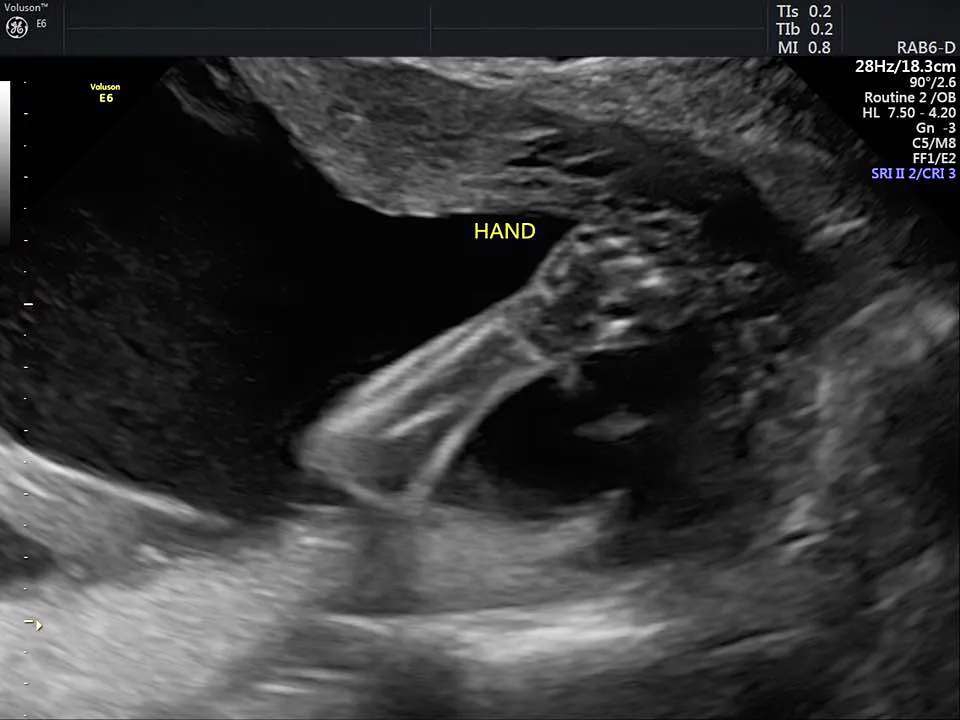

Pregnant Keri Young has been documenting her unborn daughter’s progress on Facebook, recently posting a 4-D ultrasound of the baby, who she and her husband, Royce Young, have named Eva.

The Oklahoma City couple, who are already parents of a young son, Harrison, found out at their 19-week ultrasound late last year that the girl she was carrying had anencephaly (when parts of the skull and brain do not develop properly) and will die shortly after birth. But instead of terminating the pregnancy, the pair decided to carry the baby to term so they can donate her organs after she dies.

“This is our daughter’s perfect heart. She has perfect feet and perfect hands. She has perfect kidneys, perfect lungs and a perfect liver. Sadly, she doesn’t have a perfect brain. We found out recently she has anencephaly and is terminal. Faced with terrible options we have decided to continue the pregnancy to full term so Eva, which literally means life, can grow strong and give life to multiple people through organ donation.”